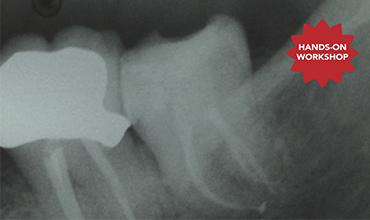

Prof Hom Lay Wang - Predictably Successful Periodontal, Oral Plastic And Implant Surgical Course

Prof Hom Lay Wang is ranked as the #1 in the world on the subject of peri-implantitis based upon “Expertscape” website. Prof. Hom Lay Wang , DDS, MSD, PhD, Professor and Director of Graduate Periodontics at the University of Michigan. Prof Wang published one textbook, more than 30 book chapters/invited reviews and more than 500 scientific articles.